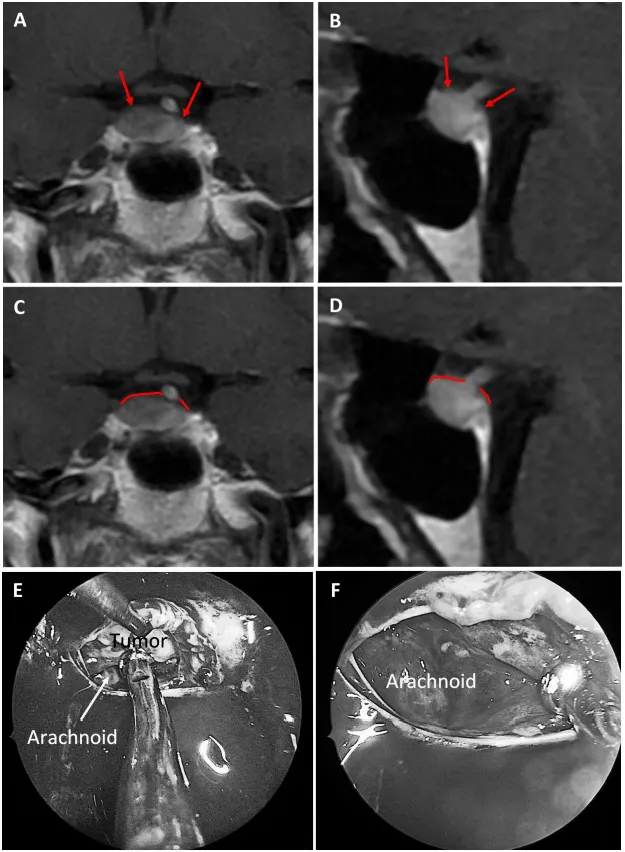

图6展示59岁女性泌乳素腺瘤患者。a和b为术前MRI图像,红色箭头指示厚度小于1毫米的强化屏障区;c和d为术前MRI,红色标记线标示薄弱屏障位置;e和f为术中图像,显示由蛛网膜构成的屏障结构。